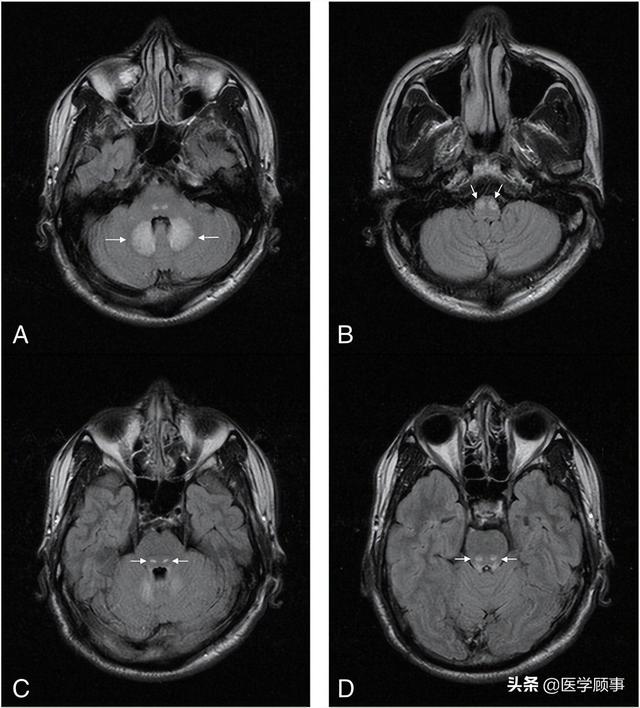

wernicke脑病的影像特点

图片尺寸640x708

wernicke脑病影像表现

图片尺寸1080x810